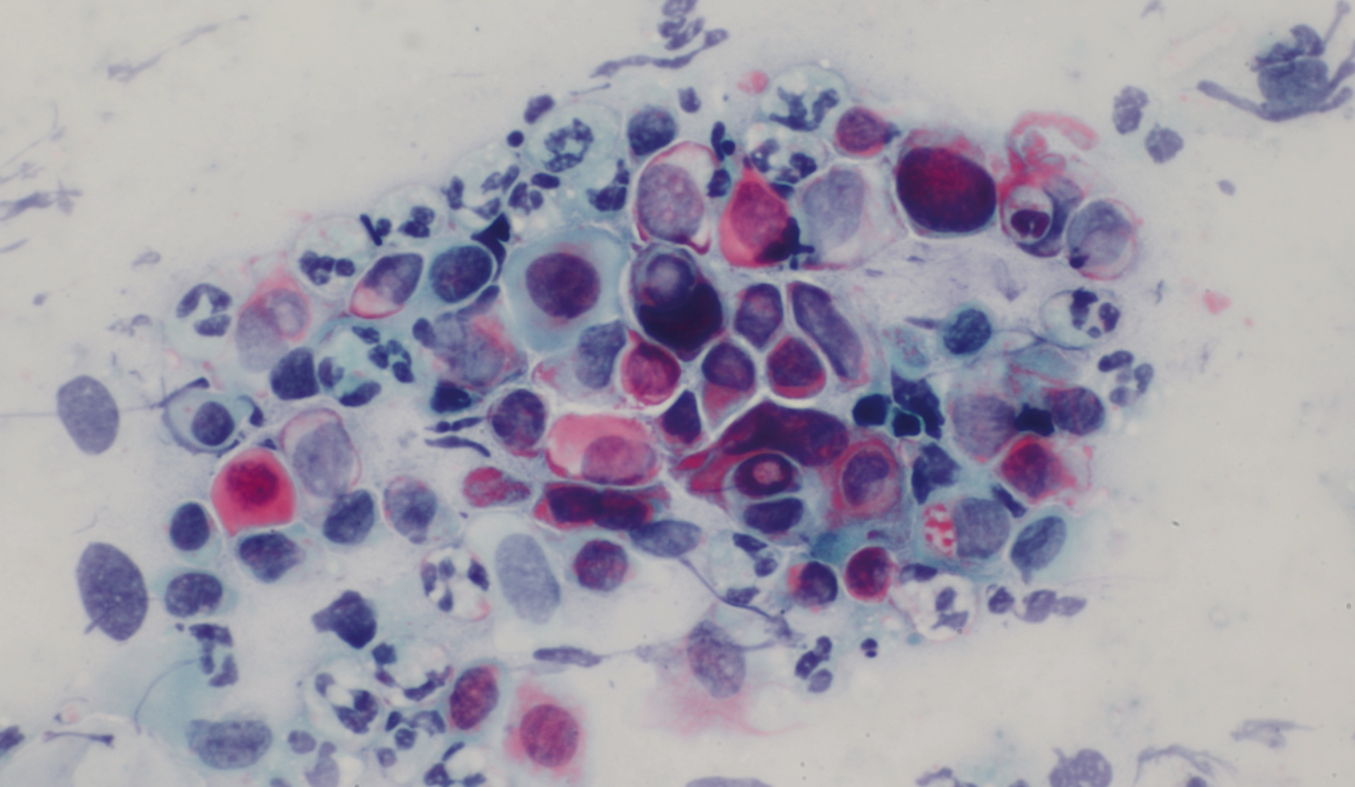

Class V-p – Cancer

Squamous cell carcinoma

Eosinophilic and basophilic squamous epithelial tumor cells with marked pleomorphism, anisokaryosis and hyperchromasia in a 37-year-old patient.